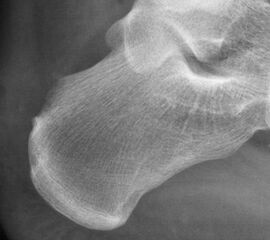

Abbildung 11-12

Prä- und postoperatives Röntgenbild.